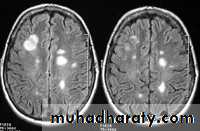

-MRI is more sensitive than CT in the demonstration of MS plaques.

- the most characteristic appearance is that of peri ventricular nodular Hyper intense lesions on T2 weighted images.

-the plaques are also well seen at the gray- white matter interfaces.

-some lesion may show a central area of greater signal intensity , resembling a target.

-contrast enhancement after giving gadolinium occurs in the acute phase indicating activity & in the chronic phase doesn't enhance.

SAGITAL FLUID ATTENUATION INVERSION RECOVERY SEQUENCE: OVOID PLAQUES ( HIGH SIGNAL INTENSITY) , WHICH ARE PERPENDICULAR TO LATERAL VENTRICLE.